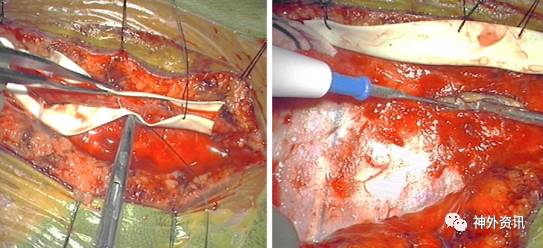

解剖受血动脉

星形剪开硬膜充分显露大脑皮质,同时在近端STA附近纵行切开硬膜容纳供血动脉穿过。每一步操作都必须彻底止血,为吻合血管营造洁净的术野。

Moyamoya病患者存在许多脑膜-皮层滋养血管,这些血管在术前颈外动脉造影不一定能显示,但是它们的存在绝不是可有可无,因此,剪开硬膜时应尽量予以保留。分离局部的蛛网膜释放脑脊液实现脑松弛,另外,广泛松解脑沟表面的蛛网膜可以促进术后新生血管形成。

选取合适的MCA皮层支进行搭桥非常重要,选择标准包括血管的可及性、管径以及近远两端是否具有良好的血管床。一般情况下,理想的受血动脉是至少0.9mm粗的M3或M4。如果STA比较大或者需要完全替代MCA的血流(高流量搭桥),M2是更合适的选择。位于发生过缺血事件和软化脑区的动脉苍白而扁平,应予以舍弃。